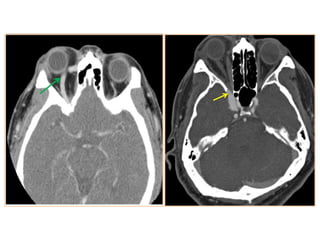

• #30 Meningioma: axial T2-wi (a) and T1-wi after contrast (b) showing a left cavernous sinus mass (white arrows) slightly hypointense on T2 sequence with strong and homogeneous enhancement. This lesion presents a dural tail anteriorly and posteriorly and totally encases the intracavernous left internal carotid artery, which is narrowed (black arrow).

• #31 T2 isointense left cavernous sinus meningioma with narrowing of the left ICA

• #41 Chondrosarcoma: large mass localized on the right petroclival fissure invading the right cavernous sinus and extending to the posterior fossa with mass effect on the pons. CT shows stippled calcifications and petrous apex erosion (a). This mass is strongly hyperintense on T2-wi (b), and shows heterogeneous enhancement after contrast (c).

• #42 Chordoma: mass centered on the clivus and the right cavernous sinus, heterogeneously hyperintense on T2-wi. (a), hypo- to isointense on T1-wi with an heterogeneous enhancement after contrast (b) corresponding to a chordoma.